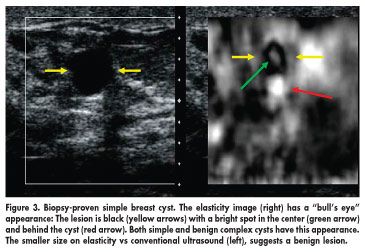

In the study, lesions were graded as malignant or benign based on the difference in their size on conventional B-mode ultrasound and elasticity imaging. If a lesion was smaller on elasticity imaging than on B-mode ultrasound, it was classified as benign (Figure 1); if larger, it was considered malignant (Figure 2).

Elasticity imaging also is providing some unique observations about breast lesions, Dr. Barr noted. Cysts, which are seen as thin-walled structures that are free of fluid on conventional ultrasound imaging, have a characteristic bull's eye appearance on elasticity, with white dots inside and posterior to the lesion (see Figure 3).